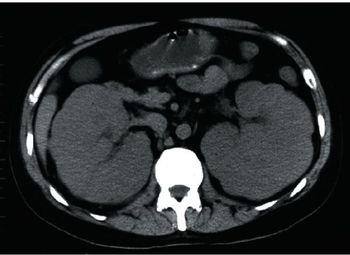

Acute Kidney Injury in Patients With Cancer

Acute kidney injury is a common complication in cancer patients, and clinicians should be familiar with the processes that cause it.